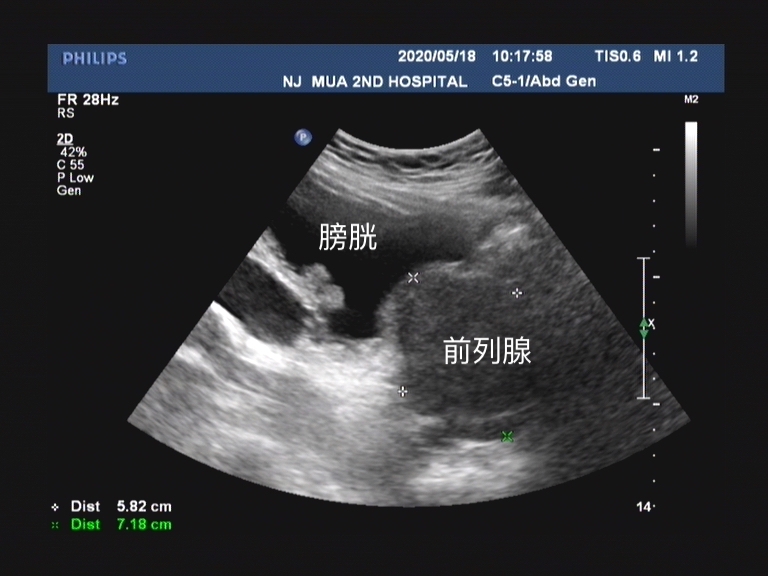

前列腺增生导致的机械性梗阻非常好理解,就是 前列腺增生时前列腺体积增大,增大的前列腺组织可挤压后尿道,前列腺部尿道伸长,变窄,排尿阻力增大。有些增生的腺体可以突入膀胱,造成膀胱出口梗阻 。经常我们和患者打比方是 “年轻的时候你的尿道如果是高速公路,那随着年龄增大,高速公路年久失修,慢慢变成了一条乡间小路” 。

这个是临床上很多患者非常关心的问题,都说非那雄胺的作用就是缩小前列腺体积, 那为什么我一直坚持在吃,但是前列腺体积每次做检查的时候仍然在增大?

总结一下,非那雄胺的适用人群是前列腺增大、下尿路症状的前列腺增生患者,前列腺体积较大(≥40ml)和/或血清PSA水平较高(PSA≥1.4ng/ml)的患者效果更好。由于非那雄胺虽然起效时间相对较慢,但是具有长期疗效稳定的特点。另外值得强调的是,虽然非那雄胺的临床作用是缩小前列腺体积,但是由于I型5α还原酶的作用,部分患者仍然会出现前列腺体积逐步增大的情况!